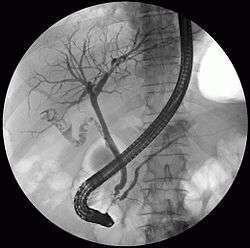

![]() ERCP image showing the biliary tree and the main pancreatic duct. | |

The biliary tree (see below) is the whole network of various sized ducts branching through the liver.

The path is as follows: Bile canaliculi → Canals of Hering → interlobular bile ducts → intrahepatic bile ducts → left and right hepatic ducts merge to form → common hepatic duct exits liver and joins → cystic duct (from gall bladder) forming → common bile duct → joins with pancreatic duct → forming ampulla of Vater → enters duodenum